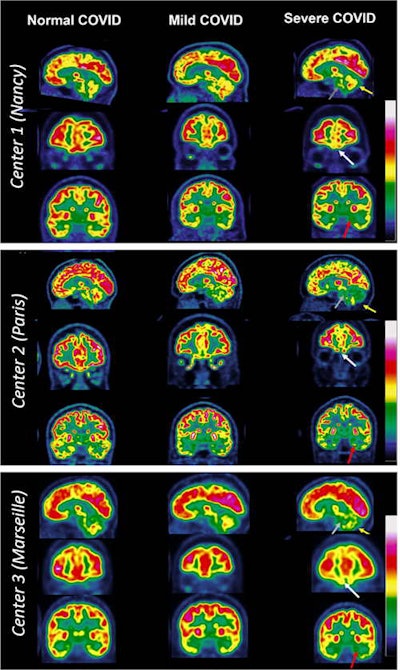

To that end, the group aimed to validate the pattern with experienced nuclear medicine physicians at three hospitals (in Nancy, Paris, and Marseille) using it to visually interpret F-18 FDG-PET imaging of suspected long-COVID patients as either normal, mildly to moderately affected, or severely affected.

Based on the visual analysis, 53% of the PET scans were interpreted as normal, 21% as mildly to moderately affected, and 26% as severely affected according to the COVID hypometabolic pattern, the researchers found.

The pattern shows hypometabolism in the fronto-orbital olfactory regions of the brain and limbic and paralimbic regions, as well as the brainstem and cerebellum, the authors wrote.

Of note, the regions affected in the PET pattern are known to be related to typical symptoms of patients with long COVID, especially olfactory loss, emotional disturbances, memory impairment, motor disorders, impaired balance, and dysfunction of autonomous behaviors, they added.